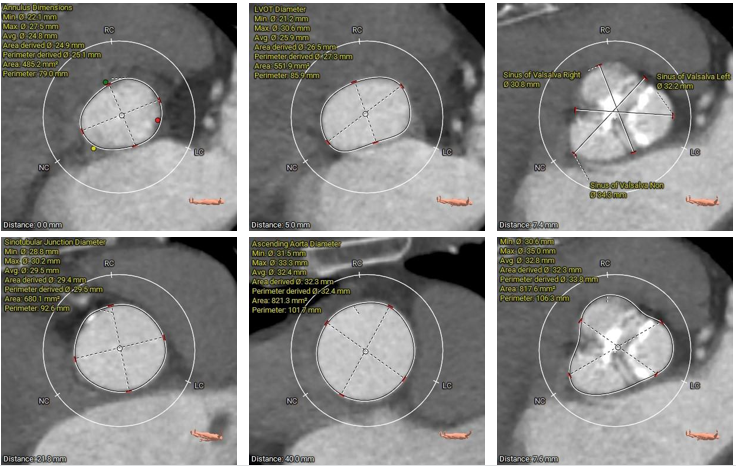

术前CT评估

type1型二叶式主动脉瓣,R-N窦纤维钙化融合嵴,瓣叶轻度增厚伴重度钙化,左冠窦瓣叶钙化较重;LVOT呈敞口型;左冠脉开口高度较低,右冠脉开口高度尚可,左冠切线位瓣叶长度>冠脉开口到瓣叶附着缘距离;瓦氏窦、窦管交界内径、升主动脉内径正常;左室腔内径尚可、心室壁未见增厚;瓣环平面与水平夹角为55°,主动脉弓夹角、弓距尚可,升主动脉未见明显扭曲;主动脉弓、降主动脉下段、双侧髂总动脉可见散在钙化斑块,左侧髂动脉轻度扭曲,股动脉穿刺处未见钙化、狭窄,入路血管直径尚可。

主动脉根部测量

瓣上结构测量

冠脉阻挡风险评估

钙化及瓣环水平夹角评估